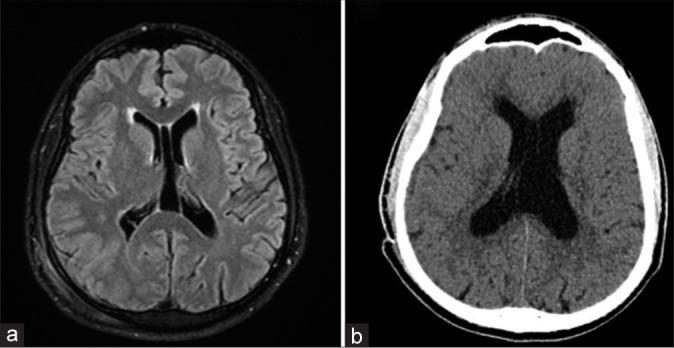

A 46-year-old reported right-sided hearing loss and a painful right retroauricular mass for 4 months. Magnetic resonance imaging revealed a 8.7 × 7.6 × 6.4 cm mass invading the right temporal and occipital bones. After a biopsy and 3 surgical procedures over 6 months, the diagnosis of TBSCC was obtained. Due to invasion of the cerebellar tissue and obstructive hydrocephalus, a ventriculoperitoneal shunt was performed. The patient was referred for adjuvant radiotherapy. However, palliative care was initiated due to tumor progression.

一名46岁患者报告右侧听力丧失和右侧耳后疼痛性肿块4个月。磁共振成像显示一个8.7×7.6×6.4 cm的肿块侵犯右侧颞骨和枕骨。经过活检和6个月内的3次手术,确诊为TBSCC。由于小脑组织受侵犯和梗阻性脑积水,进行了脑室腹腔分流术。患者被转诊接受辅助放疗。然而,由于肿瘤进展,开始了姑息治疗。